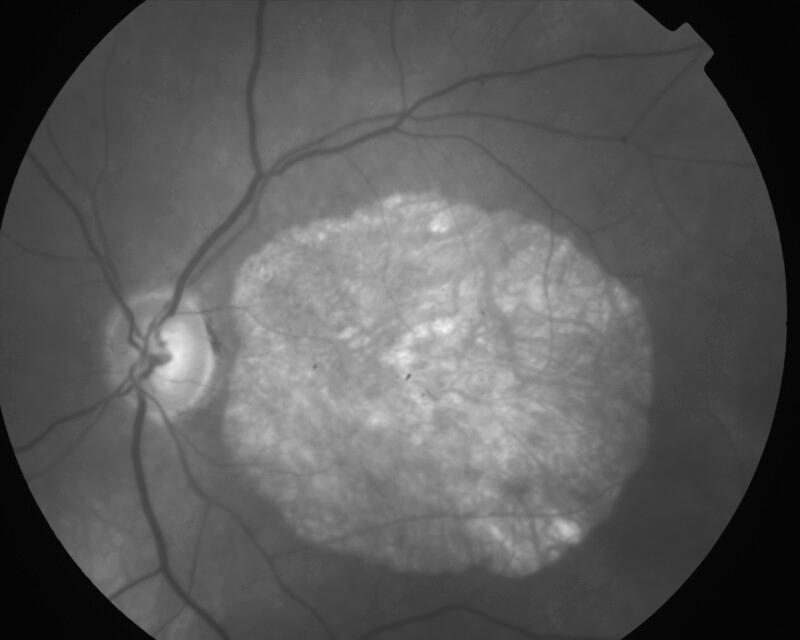

CICATRICE APRES EXERESE CHIRURGICALE DE NEOVAISSEAUX

IM000008.JPG